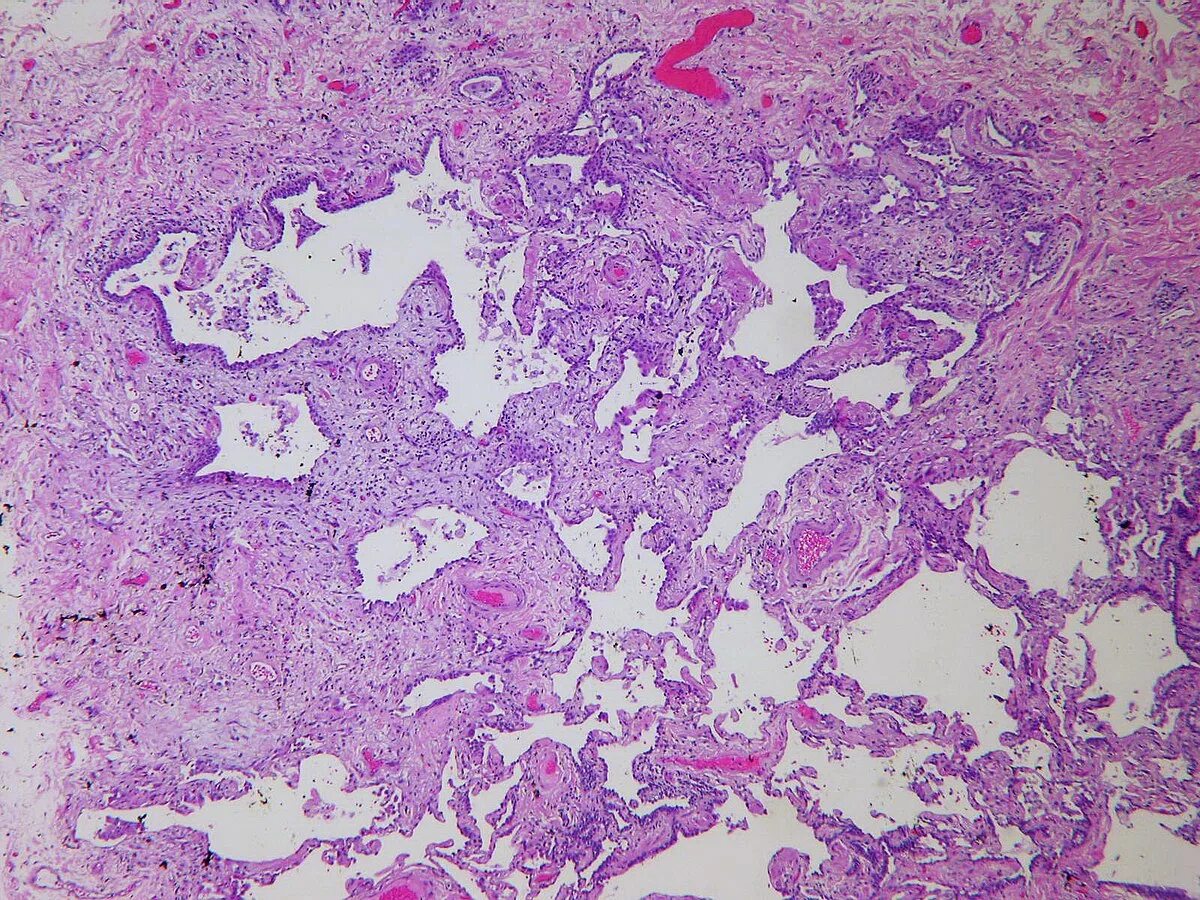

Патан пф